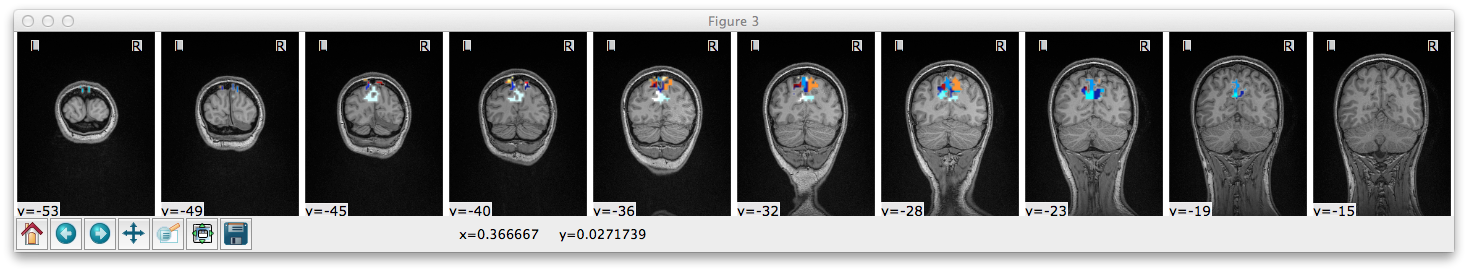

Demo of clustering pipeline

Data source was a single-subject resting state scan. Blah blah preprocessing parameters, blah. Pairwise Pearson product-moment coefficient computed for all voxels. Then this was turned into:

Note: The eta2 matrix only considers voxels in a sphere around medial parietal cortex, because I was trained by Jody Culham and parietal cortex >>> all other cortices.